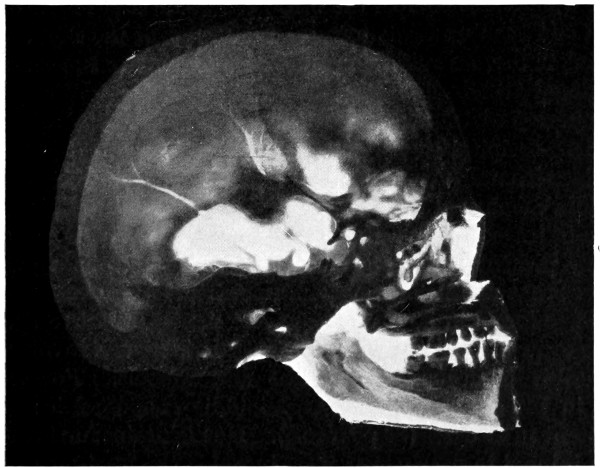

42. A comminuted fracture of the skull 112

43 A and B. An explosive fracture of the vault of the skull 113

44. A temperature chart illustrating the changes in temperature observed in head-injuries 117

45-48. Intermusculo-temporal cerebral decompression 122, 123

49 A and B. The elevation of a depressed fracture of the vault 131

50 A and B. The inner aspect of the skull and the same seen on transillumination 137